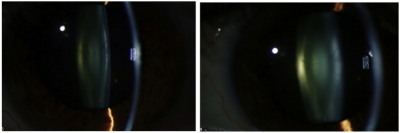

The level of alpha-crystallin in the eye declines as cataract progresses. Left: The eye of a patient with an early cataract. Right: After 20 months, the same eye has a clinically significant cataract. During that period, the level of alpha-crystallin decreased by more than 94 percent.

As we age, proteins in the lenses of our eyes start misbehaving: They unfold and congregate in clusters that block, scatter and distort light as it passes through the lens. A cloudy area, or cataract, forms. In a new study, scientists found that throughout our lifetime, levels of a key protein decline, and may be an early warning sign of a developing cataract. The study, conducted by scientists at the National Eye Institute and the Wilmer Eye Institute of Johns Hopkins Hospital and published online in Ophthalmology, suggests that there is a window before cataracts develop when there may be time to intervene and prevent them.